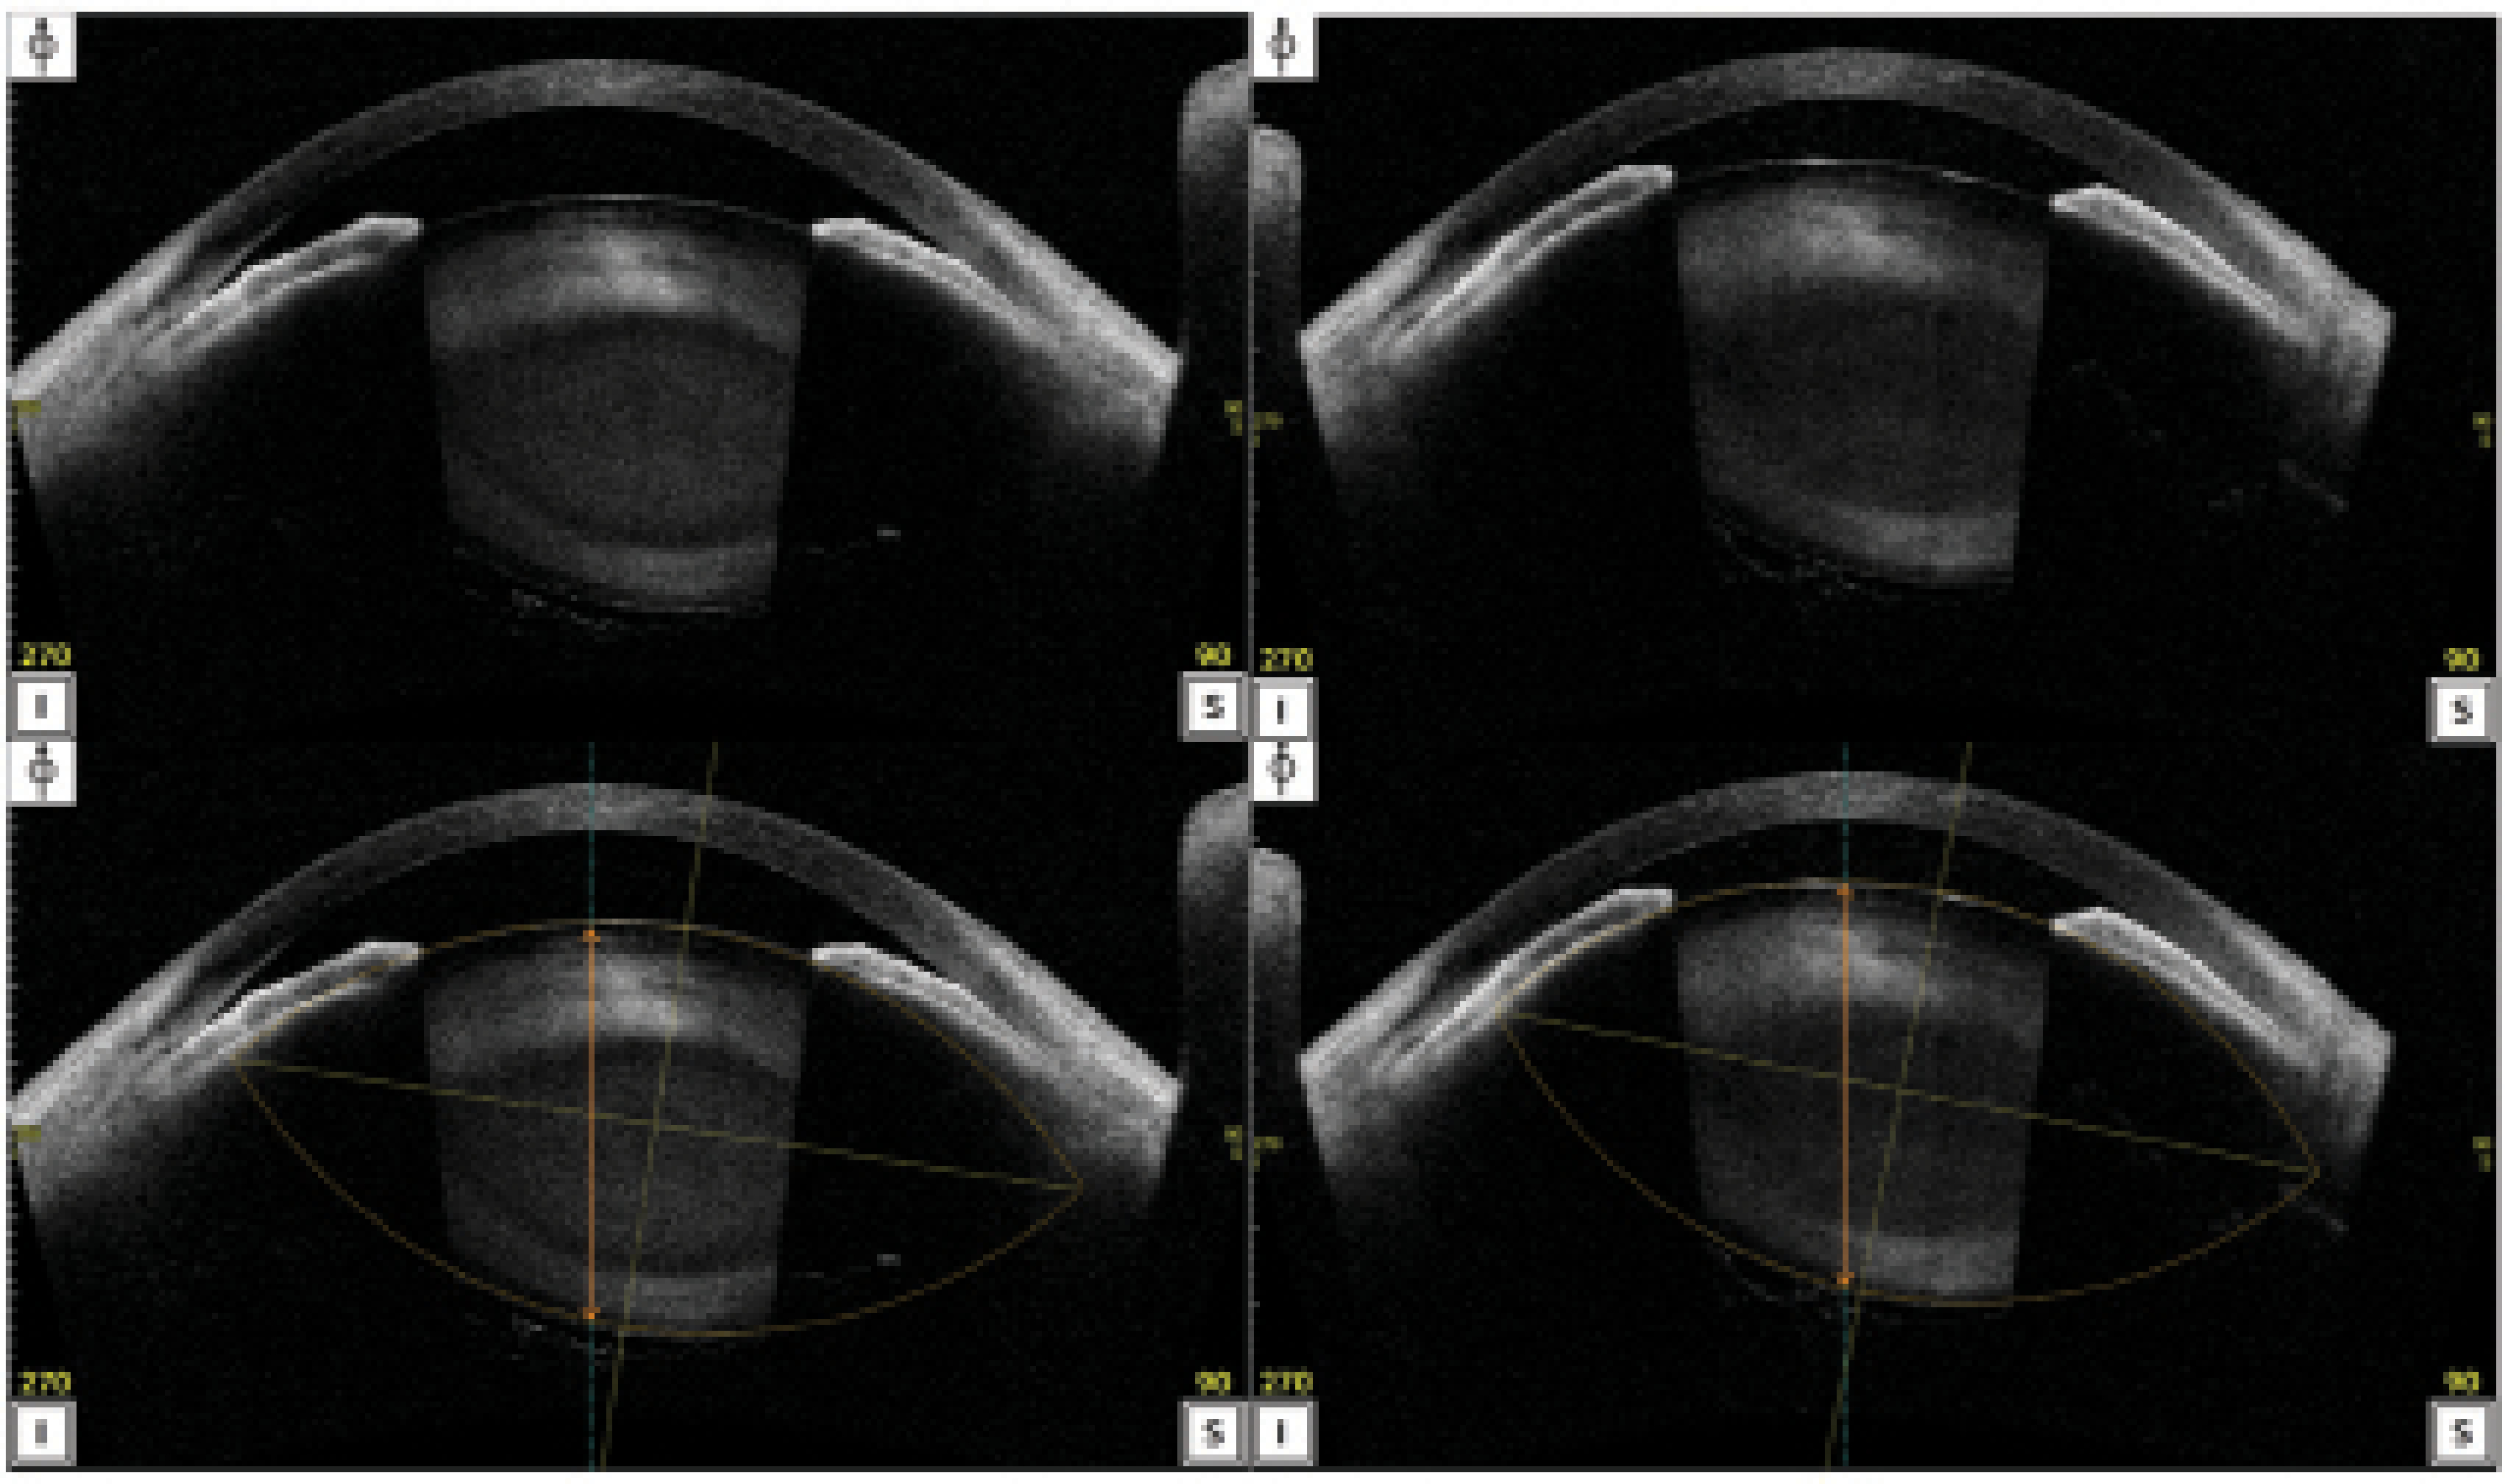

<p>Figure 2. AS-OCT images demonstrate tilt and superior decentration of the lens. A and B are the original images; C and D are lens analysis reports showing the outline and center of the lenses. The original images and the lens analysis reports were obtained 1 month apart. The images in B and D reveal a shallower anterior chamber and greater lens tilt compared to the images in A and C.</p>

Figure 2. AS-OCT images demonstrate tilt and superior decentration of the lens. A and B are the original images; C and D are lens analysis reports showing the outline and center of the lenses. The original images and the lens analysis reports were obtained 1 month apart. The images in B and D reveal a shallower anterior chamber and greater lens tilt compared to the images in A and C.